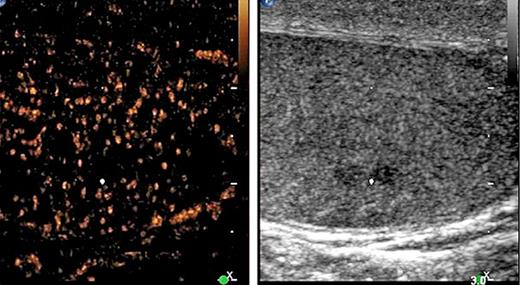

3rd patient: this 31-year-old patient underwent orchiectomy for testicular seminoma (pT3, CS1). Although markers were negative and no metastases were detected radiologically (Fig. 2a), the patient received adjuvant single-shot carboplatin therapy because of spermatic cord invasion of the primary and on grounds of personal choice of the patient. Twenty-six months thereafter he presented with a bulky retroperitoneal relapse (Fig. 2b). He was salvaged with 3 courses of BEP (bleomycin, etoposide and cisplatin) chemotherapy. It is to be noted here that the miR371a-3p level was at RQ = 3081.8 before orchiectomy and it continued to remain elevated at RQ = 351.8 five days after orchiectomy.

Then, no further decrease was recorded. At the time of the clinically apparent relapse, the level had risen to RQ = 4240.3 and it decreased to normal levels at the completion of salvage therapy and remained stable during the later course. This case was briefly reported previously [13].